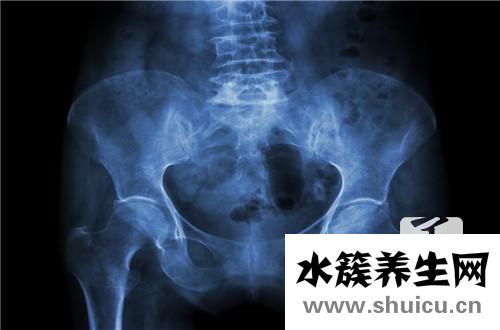

?盆腔腫塊是女性的常見婦科疾病,通常是由于長期不注意性生活衛生或長期不規律的性生活而引起的,盆腔腫塊也分為良性和惡性,需要通過醫療設備進行檢查。 骨盆腫塊很容易引起腹部腫脹,還可能導致月經不...